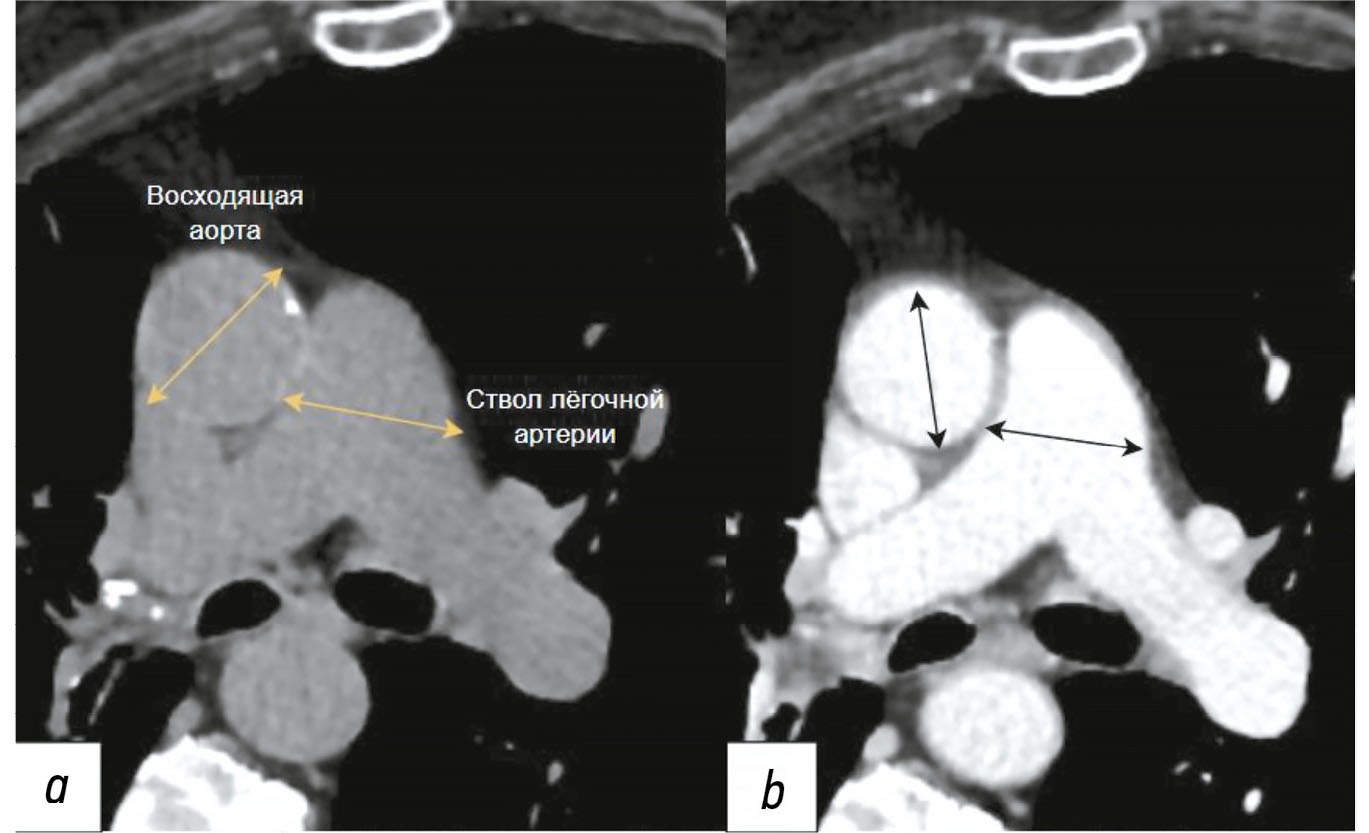

Diagnosis of thoracic aortic aneurysms and pathological pulmonary trunk dilation using chest computed tomography and artificial intelligence: modern approaches and prospects (a review)

Early diagnosis of thoracic aortic aneurysms and pathological pulmonary trunk dilation is crucial to prevent severe complications, including vascular wall rupture and acute right ventricular failure, and reduce cardiovascular mortality. This review examines contemporary imaging approaches for these conditions, focusing on computed tomography as the gold standard modality. Emphasis was placed on the implementation of artificial intelligence technologies, which enable automatic segmentation of vascular structures, measurement of their diameter, and opportunistic screening, allowing early detection of asymptomatic conditions without additional diagnostic procedures, thereby reducing radiologist workload and improving medical care quality. The study comprehensively analyzed the Moscow Experiment, wherein the application of artificial intelligence in medical image analysis showed high sensitivity, reproducibility, and reduced reporting time. Despite these significant advantages, the need for expert supervision of artificial intelligence-generated results to ensure diagnostic accuracy and reliability is emphasized. Moreover, the review highlights the importance of adapting algorithms to different scanning protocols and population-specific features. Additionally, the importance of interdisciplinary collaboration among cardiologists, radiologists, data scientists, and software developers for the effective integration into routine clinical practice is pointed out. Therefore, the review outlines the potential of artificial intelligence technologies to enhance diagnostic quality and underscores the need for further clinical research and standardization of methods for successful integration into daily practice.